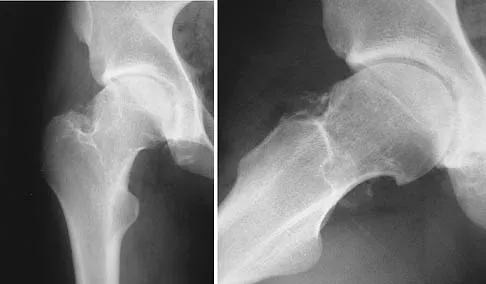

A 21-year-old collegiate female cross-country athlete reports right hip pain that begins about 12 miles into a run, followed by pain resolution when she discontinues running. However, each time she tries to resume a running program, she experiences recurrence of pain deep in the anterior groin. A plain radiograph and MRI scan are shown in Figures 8a and 8b. Management should consist of

Explanation

The history is consistent with a stress fracture. Findings on the plain radiograph are marginal, but the MRI scan shows evidence of stress reaction in the medial neck of the femur (compression side). A lesion on the compression side is not normally at risk for displacement and usually can be managed nonsurgically. A bone scan would further identify the lesion but is not necessary. A skeletal survey and chest radiograph are used in staging a tumor. Radioisotope injection and guided biopsy are sometimes used for osteoid osteomas. Boden BP, Osbahr DC: High-risk stress fractures: Evaluation and treatment. J Am Acad Orthop Surg 2000;8:344-353.